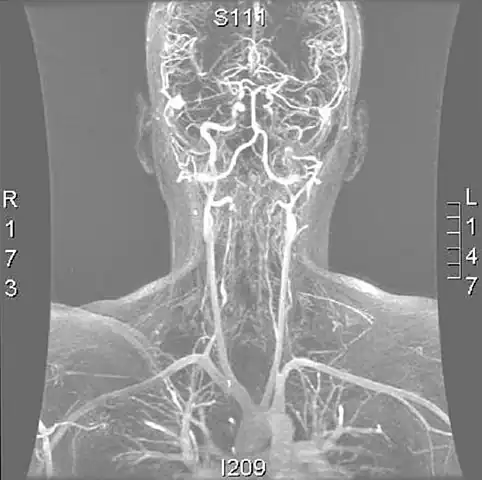

Vertebral artery dissection with focal dilatation of involved segment

Magnetic resonance angiogram of the neck vessels in a person with Ehlers-Danlos syndrome type IV; it shows a dissection of the left internal carotid artery, dissection of both vertebral arteries in their V1 and V2 segments and a dissection of the middle and distal third of the right subclavian artery. Such striking episodes of dissection are typical for this "vascular" subtype of Ehlers-Danlos syndrome.

A reconstruction of the vertebral arteries from a CT scan, seen from the front. From the bottom, V1 is from the subclavian artery to the foramina, V2 is from the foramina to the second vertebra, V3 is between the foramina until entry into the skull, and V4 is inside the skull embedded in the dura mater. They merge into the basilar artery, which then divides into the posterior cerebral artery.